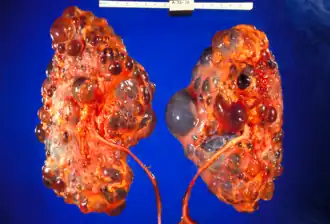

Reins polykystiques gravement affectés enlevés au moment de la transplantation

Kystes peuvent se former avant la naissance, pendant l'enfance ou à l'âge adulte[5]. Lorsque les kystes se développent avant la naissance , un retard de croissance ou des problèmes respiratoires peuvent survenir[3]. Sinon, les symptômes peuvent inclure des douleurs au flanc, du sang dans les urines et des maux de tête [2]. Les complications peuvent inclure une insuffisance rénale, une hypertension artérielle, des kystes hépatiques, un anévrisme aortique et un anévrisme cérébral [1].

Il survient à la suite d'une mutation génétique [1]. Généralement, cela est hérité des parents d'une personne, bien que cela puisse rarement se produire spontanément au cours du développement précoce [1]. Les kystes se forment à partir de tubules non fonctionnels dans lesquels du liquide est pompé[6].